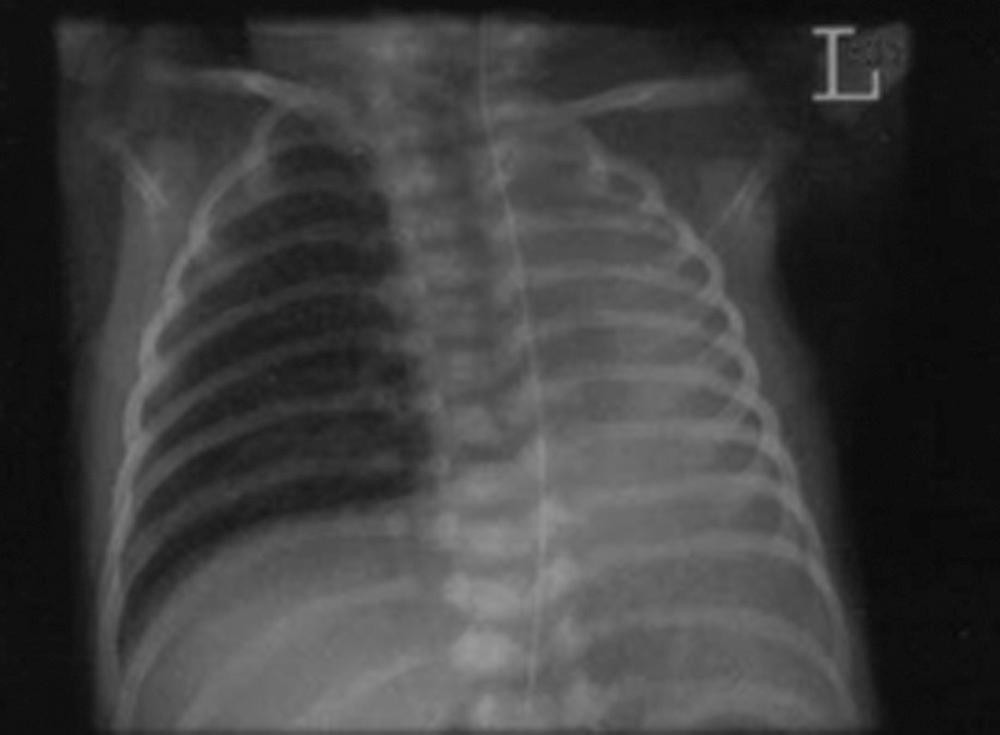

Diagnosis is confirmed on antenatal ultrasound by the presence of mediastinal shift in the absence of a diaphragmatic hernia. Antenatal echocardiogram reveals total absence of the pulmonary artery or one of its branches on the affected side. Magnetic resonance imaging (MRI) examination can confirm the diagnosis, evaluate the size of the remaining lung, and evaluate the presence of other congenital malformations. After delivery, diagnosis of infants with unilateral pulmonary agenesis can be suspected by decreased breath sounds and displacement of the mediastinum to the affected side. Some breath sounds, however, may be audible over the affected side if a portion of normal lung, which usually has undergone compensatory hypertrophy, has herniated across the midline into the affected hemithorax. The radiographic appearance of a radiopaque hemithorax helps confirm the diagnosis, and accompanying vertebral defects are not uncommon ( Fig. 66.1 ). Treatment is largely supportive, and the prognosis depends on the presence or absence of other anomalies; those with isolated pulmonary agenesis have better survival.

Fig. 66.1, Unilateral left lung agenesis.